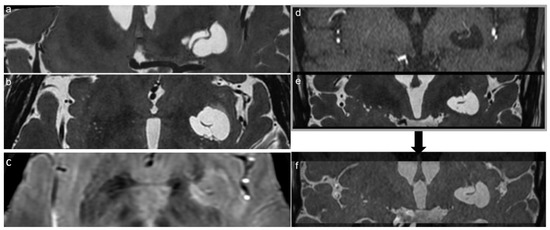

Moreover, also in our case, tractography showed compression, displacement and thinning of fiber bundle track, the inferior orbitofrontal (IFO) (Figure 3), as assessed by the difference between the total number of streamlines significantly reduced on the left.

Figure 3.

Histogram shows the Fractional Anisotropy (FA) mean value of ROIs analysis in specific structures (Cortico-spinal tract: CST; external capsule: EC; anterior thalamic radiation: ATR; uncinate fasciculus: UF), right side value in red and left value in blue. In the images below, it is possible to see DTI VR Fiber Tracking and DTI 32 directions CISS fusion showing displacement and thinning of the fiber bundle, in this case the inferior frontal-orbital (IFO).

Indeed, the DTI showed left displacement and decreased number of WM fibers from principal bundles in the region of interest surrounding the GTPVS with respect to the opposite side. Figure 4 illustrates the axial directionally encoded color FA map, as reported by other authors. The GTPVS mass effect is responsible for both thinning, compression and distortion of WM fibers and modifications of FA, with an apparent decrease in their number rather than real damage [12,19]. The absence of symptoms in our patient agrees with as described previously [8,12], confirming the earlier hypothesis so that tensor abnormalities do not correlate with any clinical signs or symptoms [8] and do not necessarily predict any pathological condition [12].

Figure 4.

Histogram of FA mean value (left blue and right red) of tractography maps obtained between Thalamus-like seed mask and external capsule-like termination mask. FA: Fractional Anisotropy; L: Left; R: Right. Probabilistic tractography from Thalamus as seed region and external capsule as target mask for both sides (blue on the left side and red on the right side). Green ROI highlights the GTPVS. MNI: Montreal Neurologic Institute coordinate system.